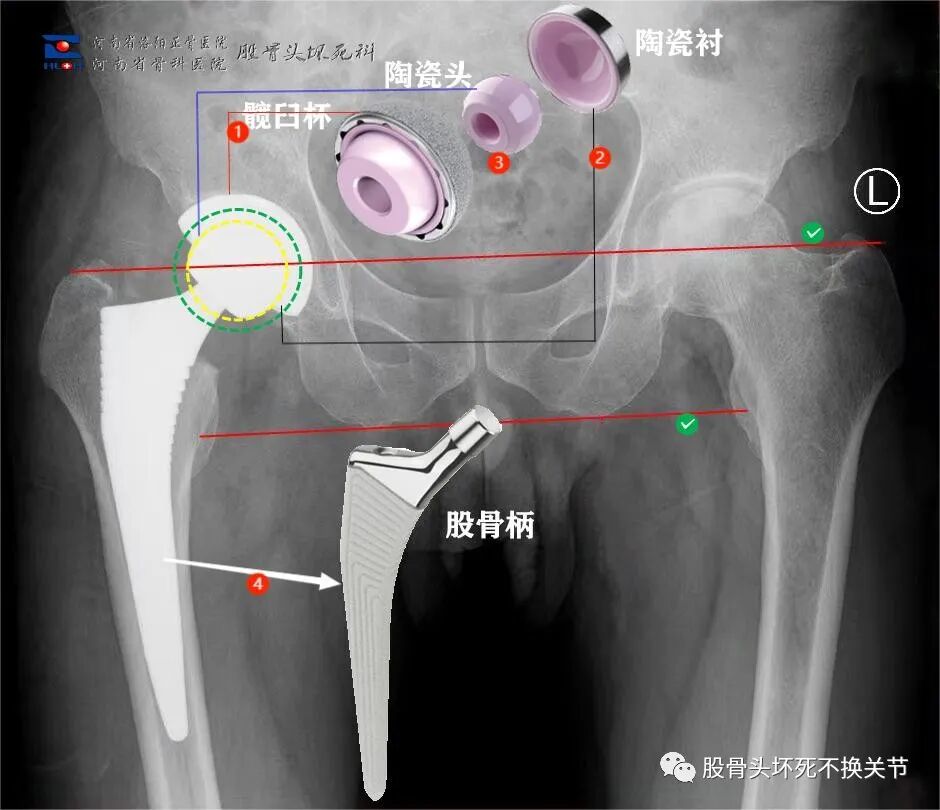

人工髋关节,分成两大部分:固定组件和摩擦界面

• 固定组件:髋臼杯①、股骨柄④,有时还会在臼杯上安装钉子以辅助固定;

• 磨损界面:髋臼内衬②、股骨头③,根据不同的配置,内衬可以是陶瓷材质,也可以是聚乙烯或高交联聚乙烯,股骨头可以是金属头或陶瓷头。